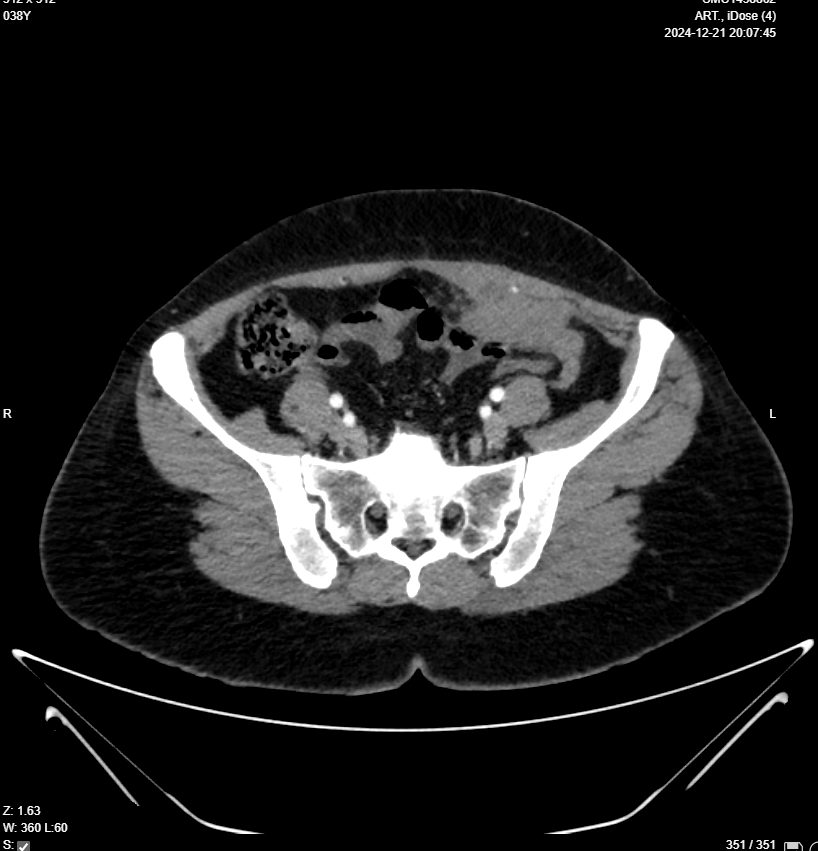

Chest, Abdomen & Pelvic CT With IV Contrast

Clinical data: Malignant LEFT OVARIAN MASS KINDLY FOR PRE RX STAGING

- Evidence of 6 X 4 X 3cm multilocular mass in Lt lower abdomen, arises from Lt adnexa “attached to uterus and Lt ovary”, invades posterior aspect of Lt rectus muscle, in contact with Lt inferior epigastric artery, also in contact with loop of small intestine with no frank invasion, this mass has surrounding fat stranding, which makes it possible to be infection like tubo-ovarian abscess, although malignancy can not be excluded, lab studies and MRI is suggested for further evaluation please.